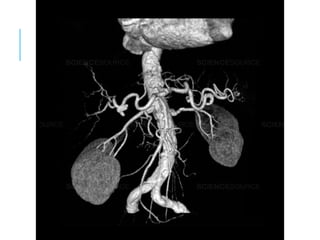

CT ANGIOGRAM

DIGITAL SUBTRACTION

ANGIOGRAPHY

VOLUME

RENDER

ED

SURFAC

E

SHADED

CT

ANGIOG

RAM OF

THE

MAJOR

BRANCH

ES OF